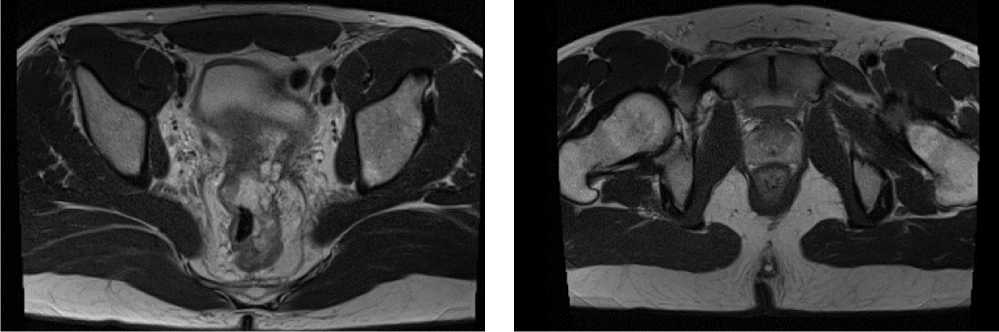

С учетом результатов ИГХ, прогрессирования процесса по результатам контрольных обследований, пациенту начата 2 линия системного лечения пембролизумабом в монорежиме.

С ноября 2022 г. выполнено 14 введений пембролизумаба с максимальным эффектом частичный регресс (образование между передней поверхностью прямой кишки и задней поверхностью предстательной железы регрессировало полностью). По результатам контрольных обследований (КТ ОБП и МРТ ОМТ от сентября 2023 г.) сохраняются очаги в печени до 21 × 11 мм, а также опухоль средне- и верхнеампулярного отделов прямой кишки с выраженным муцинозным компонентом. МР-стадия Т4а (CRM+, EMVI+) (рис. 9, 10).

Рис. 9. Частичный регресс, по данным компьютерной томографии органов брюшной полости, на фоне иммунотерапии пембролизумабом у пациента 38 лет с диагнозом метастатический колоректальный рак с признаками микросателлитной нестабильности (сентябрь 2023 г.)

Fig. 9. Partial response according to abdominal CT scan data during immunotherapy with pembrolizumab in a 38-year-old patient with metastatic MSI-H colorectal cancer (September 2023)

Рис. 10. Частичный регресс, по данным магнитно-резонансной томографии органов брюшной полости, на фоне иммунотерапии пембролизумабом у пациента 38 лет с диагнозом метастатический колоректальный рак с признаками микросателлитной нестабильности; МР-стадия Т4а (CRM+, EMVI+) (сентябрь 2023 г.)

Fig. 10. Partial response according to abdominal magnetic resonance imaging during immunotherapy with pembrolizumab in a 38-year-old patient diagnosed with metastatic MSI-H colorectal cancer; MR stage T4a (CRM+, EMVI+) (September 2023)